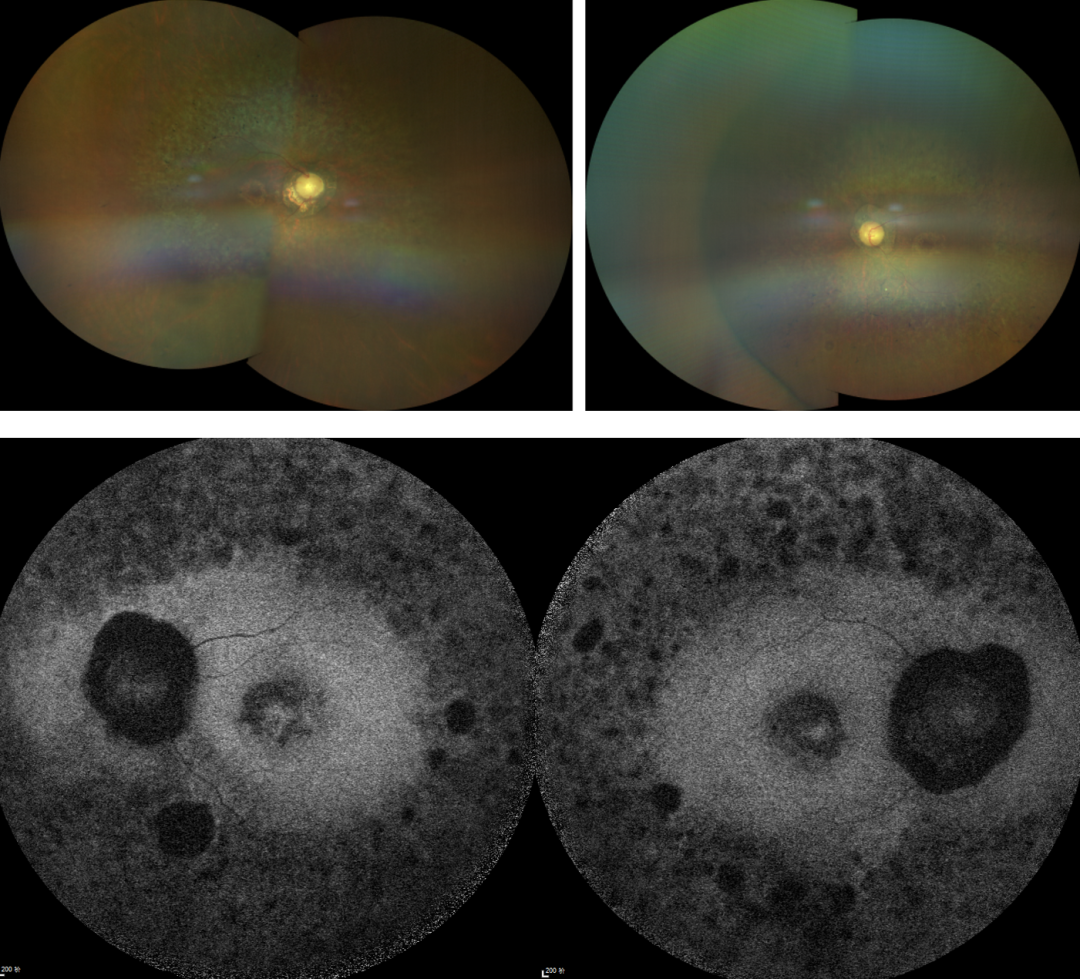

RP的診斷主要依靠眼底檢查、視野檢查、視網(wǎng)膜電圖(ERG)和基因檢測(cè)。眼底檢查可見(jiàn)典型的"骨細(xì)胞樣"色素沉著,ERG顯示視網(wǎng)膜功能下降,基因檢測(cè)可確定具體的突變基因。

視網(wǎng)膜色素變性